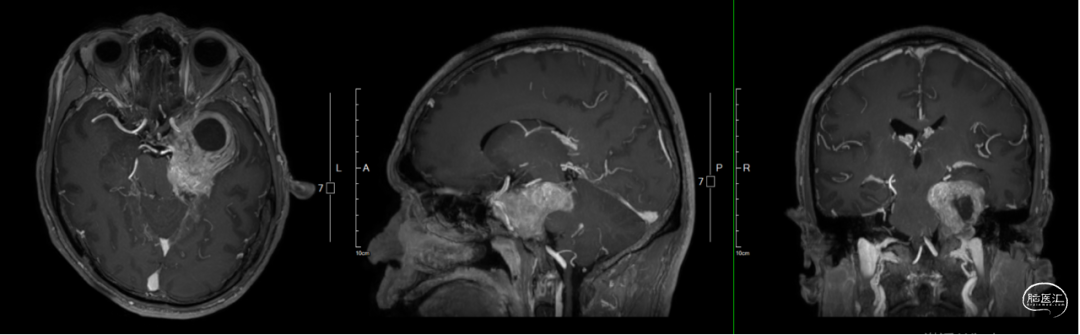

术前影像学资料

病灶横跨中后颅窝,囊实性为主,膨胀生长,部分蝶骨、岩骨及床突吸收破坏,病变通过Meckel’s腔由中颅窝及海绵窦区向后颅窝生长,脑干受压。

手术入路选择:患者病灶大,囊实性,T2提示实性部分含水量低,质地可能硬韧,病灶靠近大脑中动脉及颈内动脉,病灶横跨中后颅窝,Meckel’s周围骨质破坏,自然通道较大,故综合考虑选择扩大中颅窝入路经硬膜外切除病灶。

术前诊断:左侧中后颅窝占位:三叉神经鞘瘤?